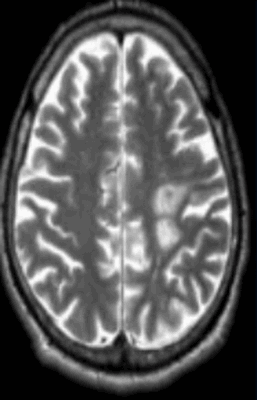

МР-снимок показывает дистрофические изменения белого вещества вокруг желудочков мозга, характерные для хронической ишемии (лейкоареоз)

Хроническая ишемия головного мозга - прогрессирующее состояние, имеющее стадийность развития. Причиной с высокой долей вероятности могут быть атеросклеротические изменения артерий, гипертония и колебания глюкозы крови.

Нейровизуализационные методы: КТ, МРТ головного мозга, МР-ангиография (артерии и вены головного мозга ), при необходимости рентгеноконтрастная церебральная ангиография. Нейровизуализация позволяет исключить другие заболевания (опухоль, гидроцефалию) и подтвердить сосудистый характер нарушений. Предпочтительнее МРТ головного мозга, на которой выявляются характерные для хронической ишемии мозга изменения:

- лейкоареоз — изменение белого вещества вокруг желудочков головного мозга (на рисунке 1, белое свечение вокруг желудочков);

- лекоэнцефалопатия — поражение белого вещества головного мозга (на рисунке 1 и 3, светлые участки в подкорковом веществе);